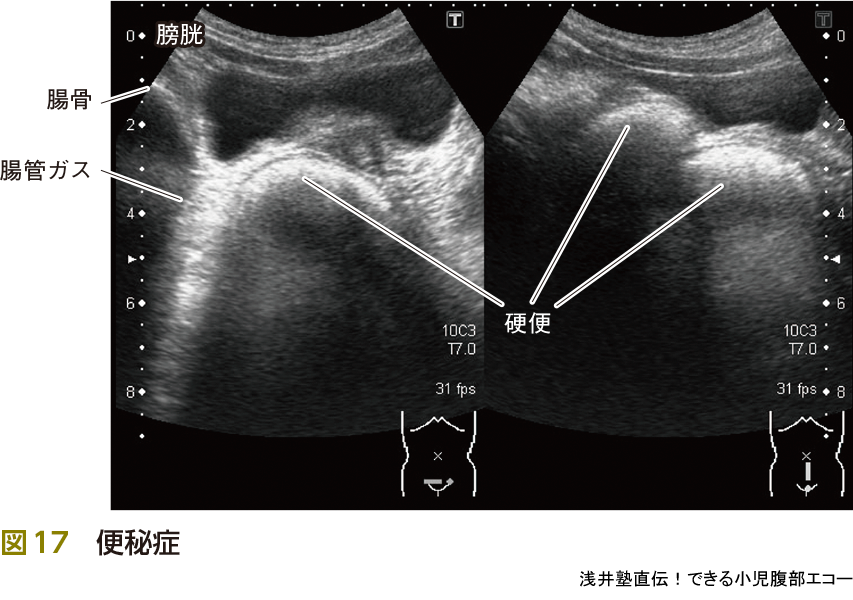

3)便秘

便秘は最も遭遇することが多い疾患の1つです(図17).たかが便秘,されど便秘です.下痢(や遺糞症)を主訴として受診する場合もあります(ピットフォール③参照).

また,便秘症は病歴と触診が役に立ちます.自らの触診で便塊の貯留部位を推測し,エコーで確認(エコー輝度が高いほど硬い便),そして再度触診をして手に覚え込ませることで触診のスキルもアップします.